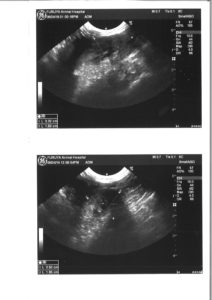

エコー:左腎に委縮があるも問題なし。心筋に若干の肥大が認められた。